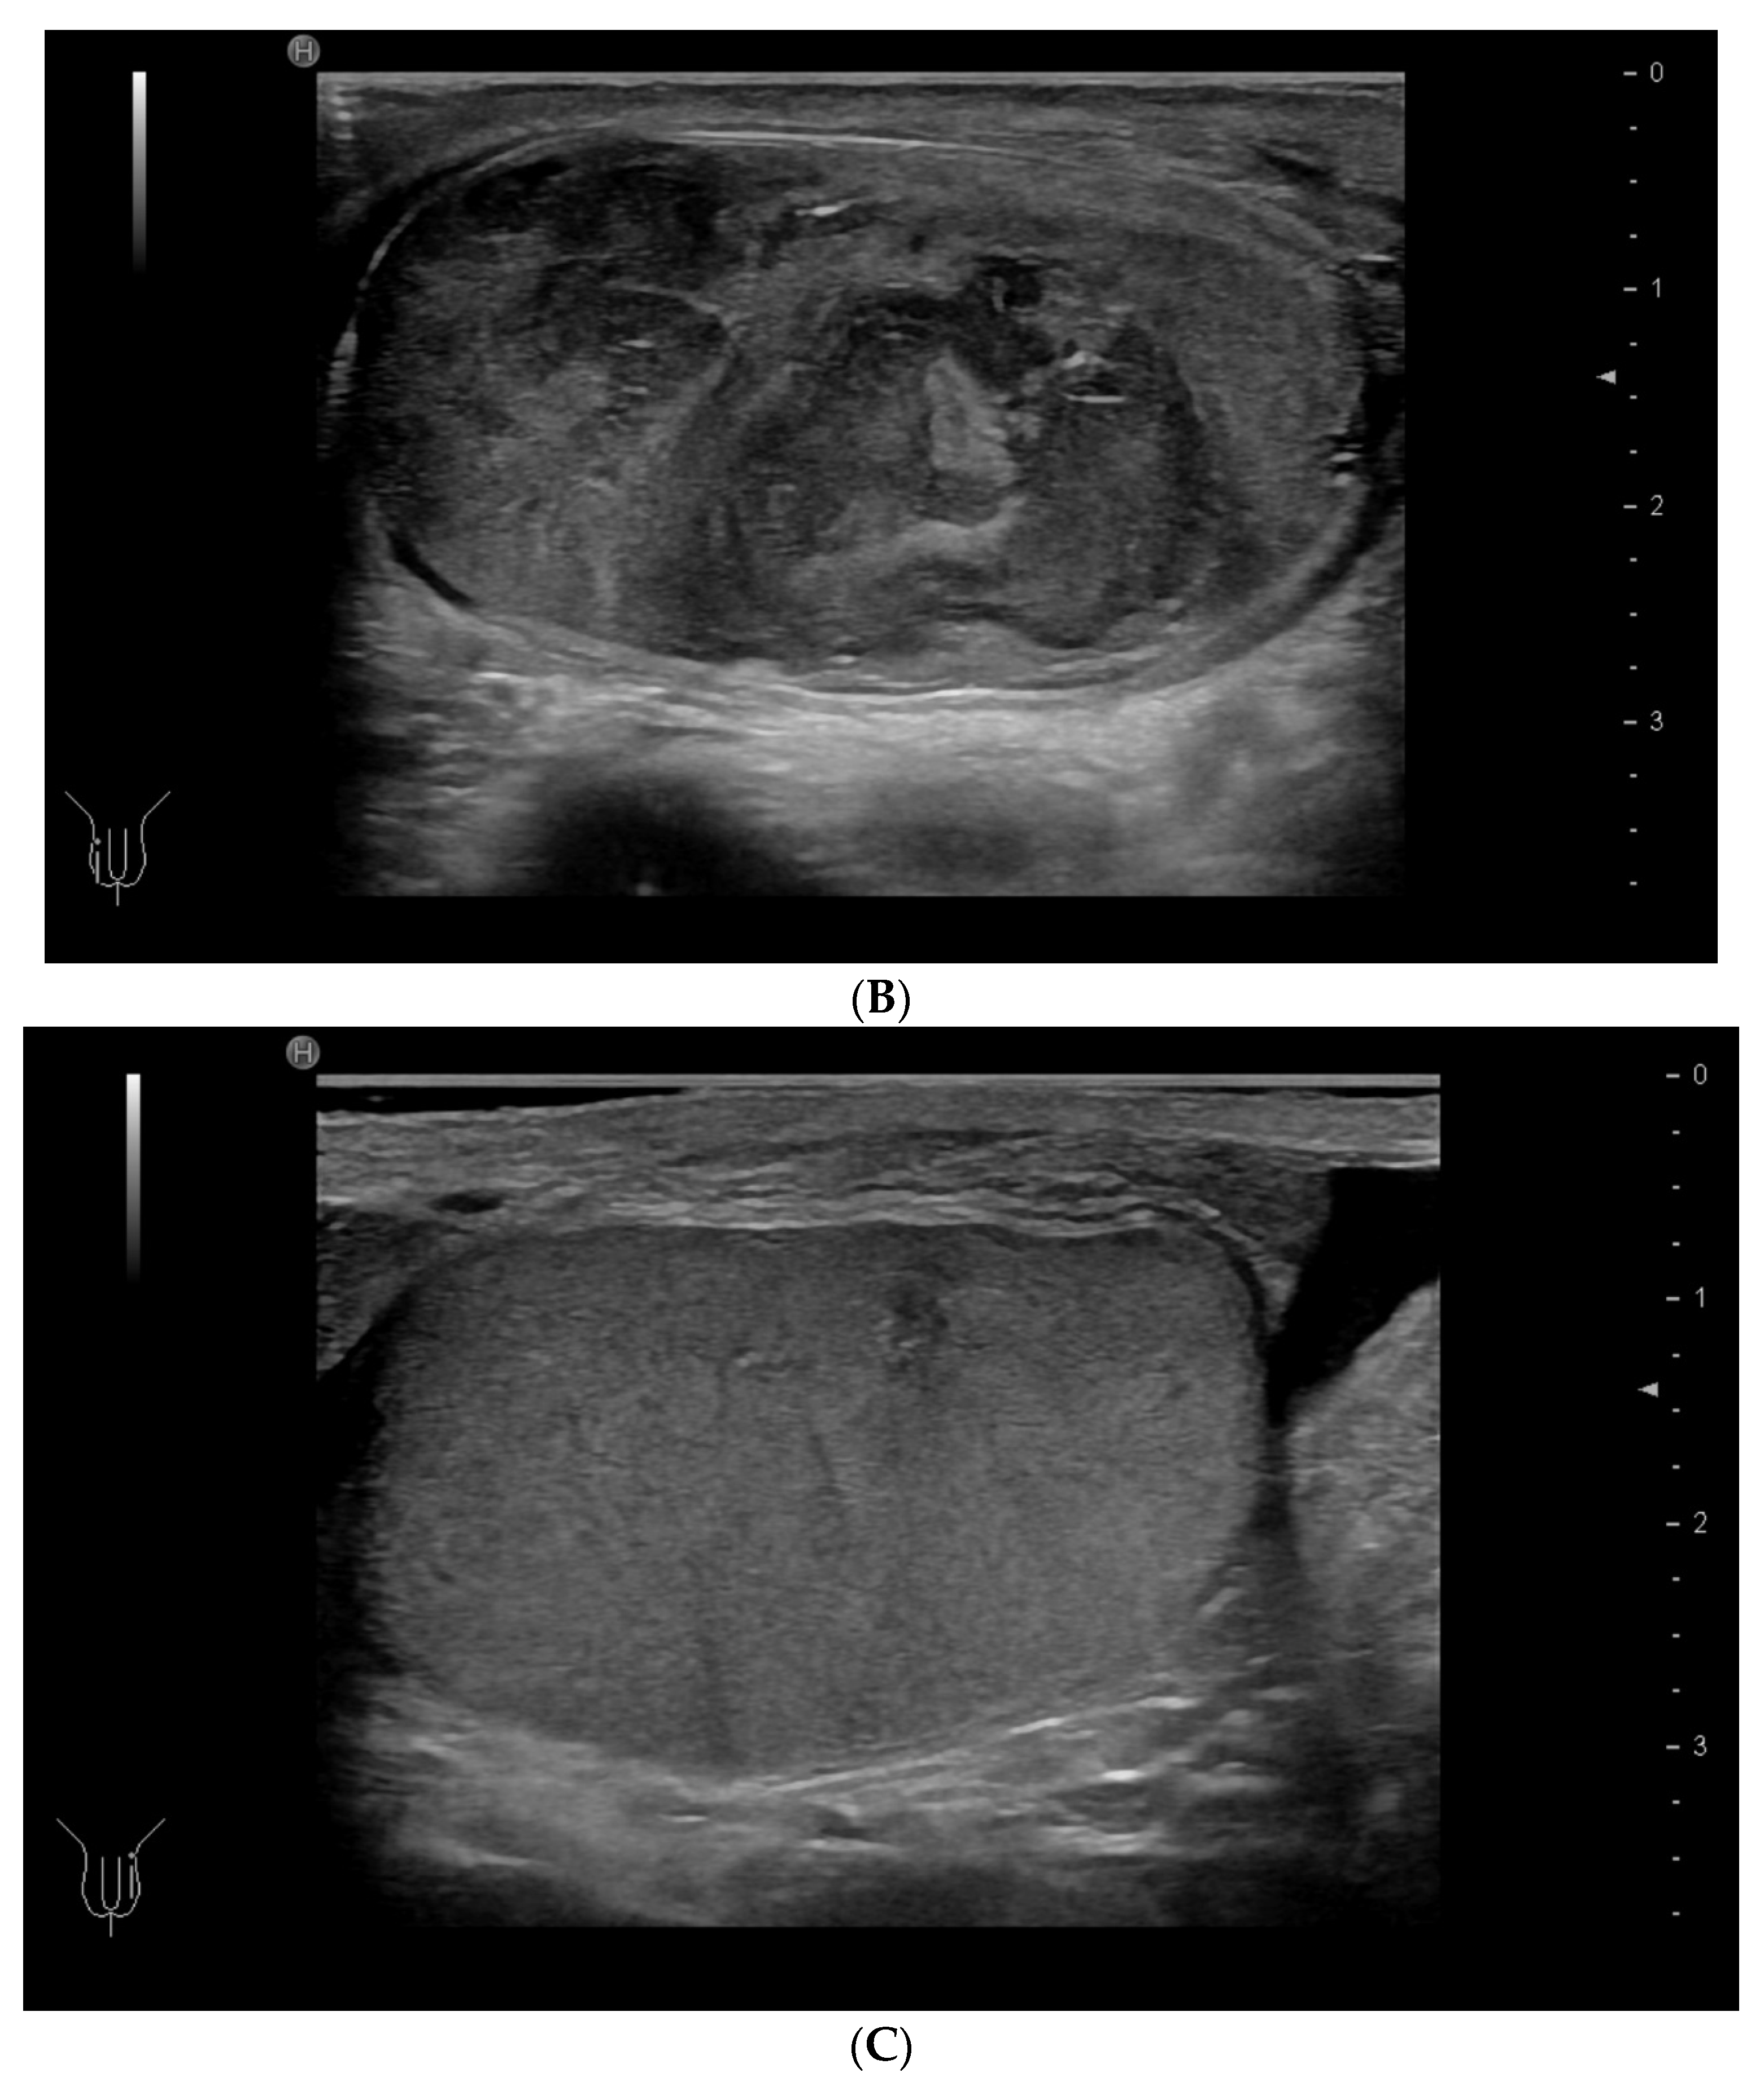

Within the scrotum, the two testicles are divided by a septum. Each testicle is oval-shaped and typically measures 4 cm in length, 3 cm in width, and 2 cm in height [64]. The anatomy of the testicles can be seen in Figure 6C, and an ultrasound image including SE is shown in Figure 6A,B. A high-frequency linear transducer is typically the preferred and best choice, but in cases with an enlarged scrotum, a curved array transducer may be a better choice.

Figure 6.

Ultrasound images of a 39-year-old male. The indication for ultrasound investigation was suspected orchitis or malignancy. The patient experienced pain in the right testicle for more than 2 days. The patient was seen in the emergency room for assessment of epididymitis and started treatment with ciprofloxacin. There was no improvement with treatment, and the right testicle became more tender and swollen. The ultrasound showed no signs of epididymitis (A). The right testicle (left side of the figure shows the elastogram, and B-mode is seen on the right side). The testicle revealed a right-sided tumour, which appeared highly suspicious using elastography (B). The B-mode image, showing a tumour (C). B-mode image of the left testicle, showing normal tissue (The pathology showed a seminoma testicular tumour with 2% of choriocarcinoma. The patient underwent surgery for removal of the right testis.